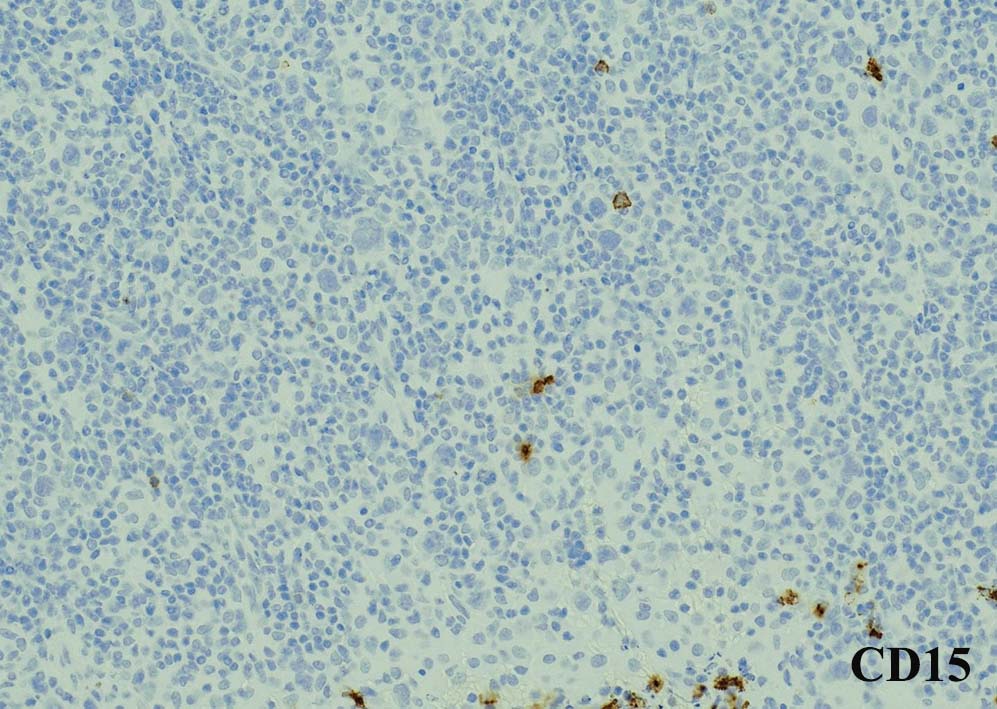

腫瘍細胞はcHLのHRS細胞のphenotypeを示す. CD20陰性. PAX5淡染, CD30+, CD15+, Fascin+, Oct2/Bob.1のいずれかが陰性.

CD30, CD15陰性. EBER-ISH陰性.